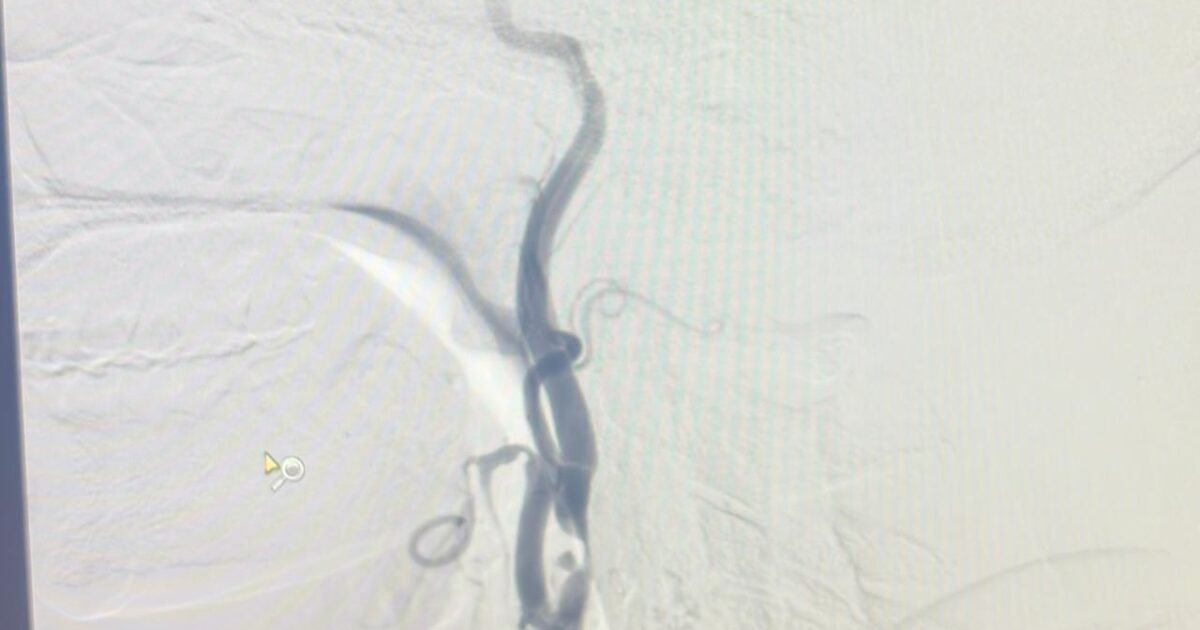

Clinical Case — Dr. Ganesh Veerabhadraiah, NeuroWellness Clinic

65-Year-Old Patient with Bilateral Carotid Stenosis

Recently, we treated a 65-year-old patient who presented with symptoms of TIA affecting the right side of the brain. Detailed imaging studies revealed:

• Severe narrowing in both carotid arteries

• An ulcerated plaque on the right side

• A floating blood clot attached to the plaque

• Adequate collateral circulation through the Circle of Willis

This was a potentially dangerous situation. A floating clot inside a carotid artery can break off at any time and travel to the brain, causing a major stroke.

Initially, carotid stenting was considered. However, in the presence of an unstable plaque and floating thrombus, stenting may carry a higher risk of dislodging the clot during the procedure.

After careful evaluation and discussion with the patient’s family, we decided that Carotid Endarterectomy would be the safest option to remove the plaque and prevent stroke.